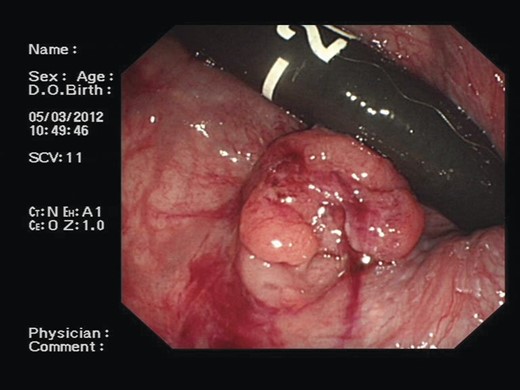

A 71-year-old asymptomatic gentleman with known history of colonic polyps underwent a follow-up surveillance colonoscopy through the BCSP. He had a background of type 2 diabetes mellitus, ischaemic heart disease and diverticular disease. Colonoscopy revealed a 1-cm firm polypoid mass at the ano-rectal junction (Fig. 1). Subsequent endoscopic mucosal resection was performed and the tissue was sent for histological analysis. This confirmed a tubulo-villous adenocarcinoma. As per national guidelines the patient underwent a staging computed tomography (CT) scan. This revealed a 10 × 15 cm homogenous mass arising from within the pelvis (Fig. 2). The mass appeared to be continuous with a neural foramen arising from the sacrum. Further imaging confirmed the mass extending into sacral segment S1 inferiorly, lumbar segments L4 superiorly and the bladder anteriorly. A regional multidisciplinary team discussion concluded that abdominoperineal resection (APR) was the most appropriate surgical approach for removal of both pathologies in their entirety.

A colonoscopic image demonstrating ∼1-cm polypoid mass at the ano-rectal junction.

The 10 × 15 cm pre-sacral pelvic mass on sagittal contrast CT.